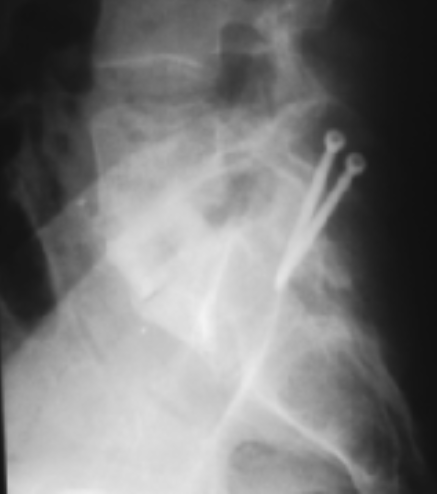

为提高融合率,多数学者建议补充后路融合和内固定(图1),从而使得前后路融合变得更加可靠[10-12]。

图1补充了后路内固定的前路融合术